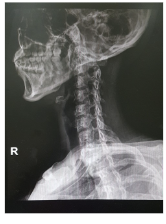

목디스크 증상 원인 치료방법 등 목 디스크 관련 정보에 대해 알아보도록 하겠습니다. 목디스크는 인간의 척추 중 경추부나 흉추부에 위치한 디스크(틀니)가 변형되어 생긴 질환으로, 경추부의 경우 목의 통증, 저림 혹은 근육 경련, 어깨와 팔의 통증, 감각상실 등이 나타나며, 흉추부의 경우 흉부의 통증, 등의 통증 등이 나타납니다. 보통은 원인불명성으로 인한 자연적인 회복을 기다리는 것이 가장 좋으며, 통증이 심한 경우 보조적으로 항통제나 근육 이완제 등을 사용합니다. 만약 압력이 심한 경우 수술이 필요할 수 있습니다.예방법으로는 바른 자세 유지와 체중 조절, 충분한 운동, 목과 등의 근육 강화 등이 있습니다.

목 디스크는 경추부나 흉추부의 디스크(틀니) 변형으로 인해 발생하는 질환으로, 다음과 같은 증상이 나타날 수 있습니다.